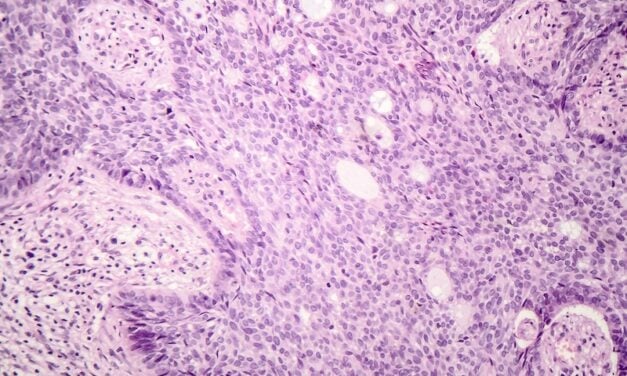

Gestalt and Primaa have partnered to integrate AI-powered dermatopathology tools in the PathFlow platform, enhancing skin cancer diagnostics.